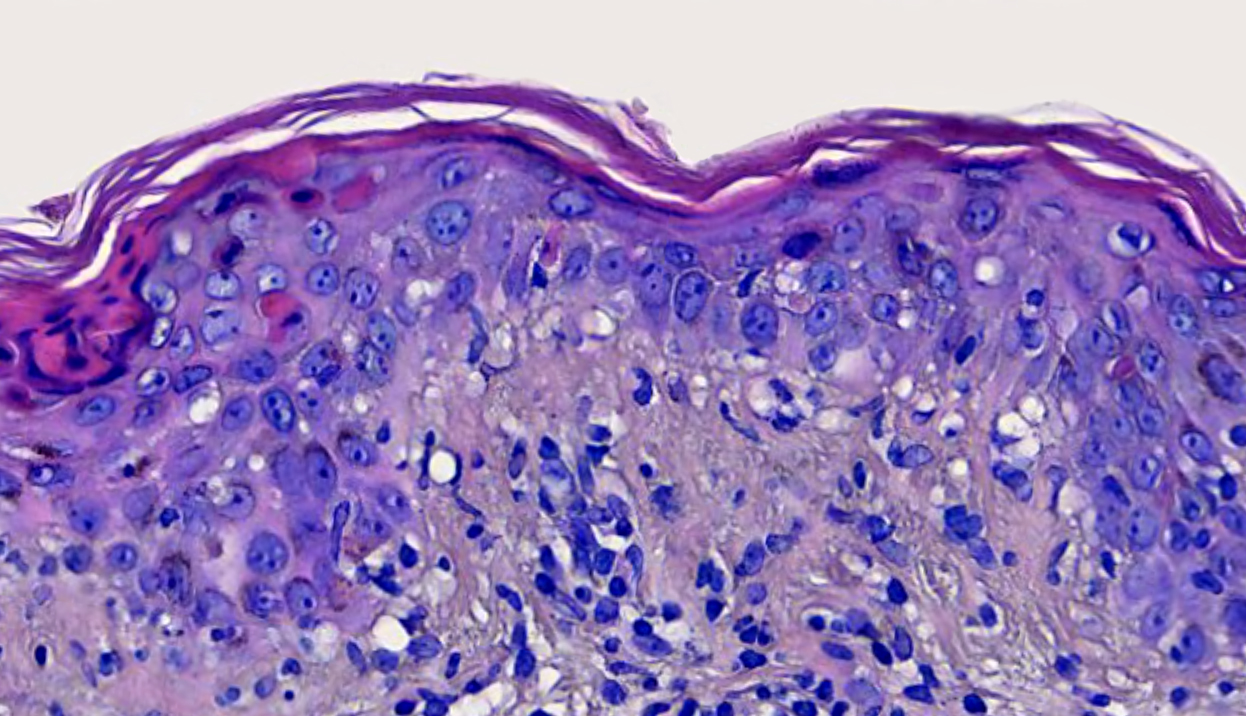

Microscopic (histologic) description

- Interface dermatitis with variable degrees of basal layer vacuolization and scattered cytoid bodies (Lupus 2012;21:577)

- Occasionally, basal layer vacuolation and keratinocyte apoptosis may be so severe that full thickness epidermal necrosis may result, generating a differential diagnosis of erythema multiforme

- Dyskeratotic keratinocytes extending into upper spinous layers is a very characteristic but rare finding of SCLE (J Cutan Pathol 2001;28:1)

- Superficial and sometimes superficial and deep perivascular lymphocytic infiltrate (Dermatol Ther (Heidelb) 2021;11:131)

- Periadnexal mononuclear cell infiltrate may be present (Dermatol Ther 2021;11:131)

- Dermal mucin, which may be highlighted with Alcian blue or colloidal iron

Microscopic (histologic) images

A 35 year old woman presents with multiple nonscarring erythematous annular plaques that arise in photo exposed areas 8 weeks after introducing terbinafine for treatment of onychomycosis. A biopsy of one of the lesions was performed (shown above). What is the most likely diagnosis?

Board review style question #2

A 50 year old man with a history of recent onset hypertension treated with enalapril presented with a 1 month history of annular and erythematous polycyclic plaques with peripheral scale that were located in sun exposed areas. No other systemic manifestations were found. Serologic test results were positive for ANA, anti-Ro / SSA and anti-La / SSB, while negative for ds-DNA, anti-histone and anti-Smith. Which histopathological finding that can be seen in this image is more characteristic of the patient's clinical type?